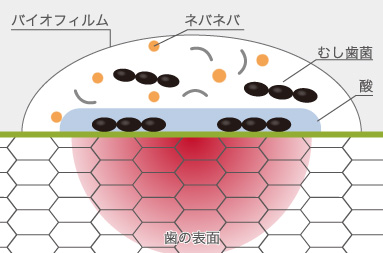

ミュータンス菌とは、食事に含まれている糖から酸を作り出す菌です。その酸によって歯が少しずつ溶けてしまいます。また、糖のない状態でも酸を作ることができ、砂糖からネバネバとした、水に溶けない物質を作り出し、歯に付着し、他のくっつく力のない細菌を巻き込んでバリヤーのようなものを作り出して、悪玉細菌の巣となる「バイオフィルム」を形成します。

むし歯は、細菌(むし歯菌=ミュータンス菌・ラクトバチラス菌)が糖分を元に作り出した酸が歯を溶かすことによって生じます。ミュータンス菌はむし歯を作り、ラクトバチラス菌はそれを進行させます。ミュータンス菌は、だ液から感染してしまいます。

ミュータンス菌とは、食事に含まれている糖から酸を作り出す菌です。その酸によって歯が少しずつ溶けてしまいます。また、糖のない状態でも酸を作ることができ、砂糖からネバネバとした、水に溶けない物質を作り出し、歯に付着し、他のくっつく力のない細菌を巻き込んでバリヤーのようなものを作り出して、悪玉細菌の巣となる「バイオフィルム」を形成します。